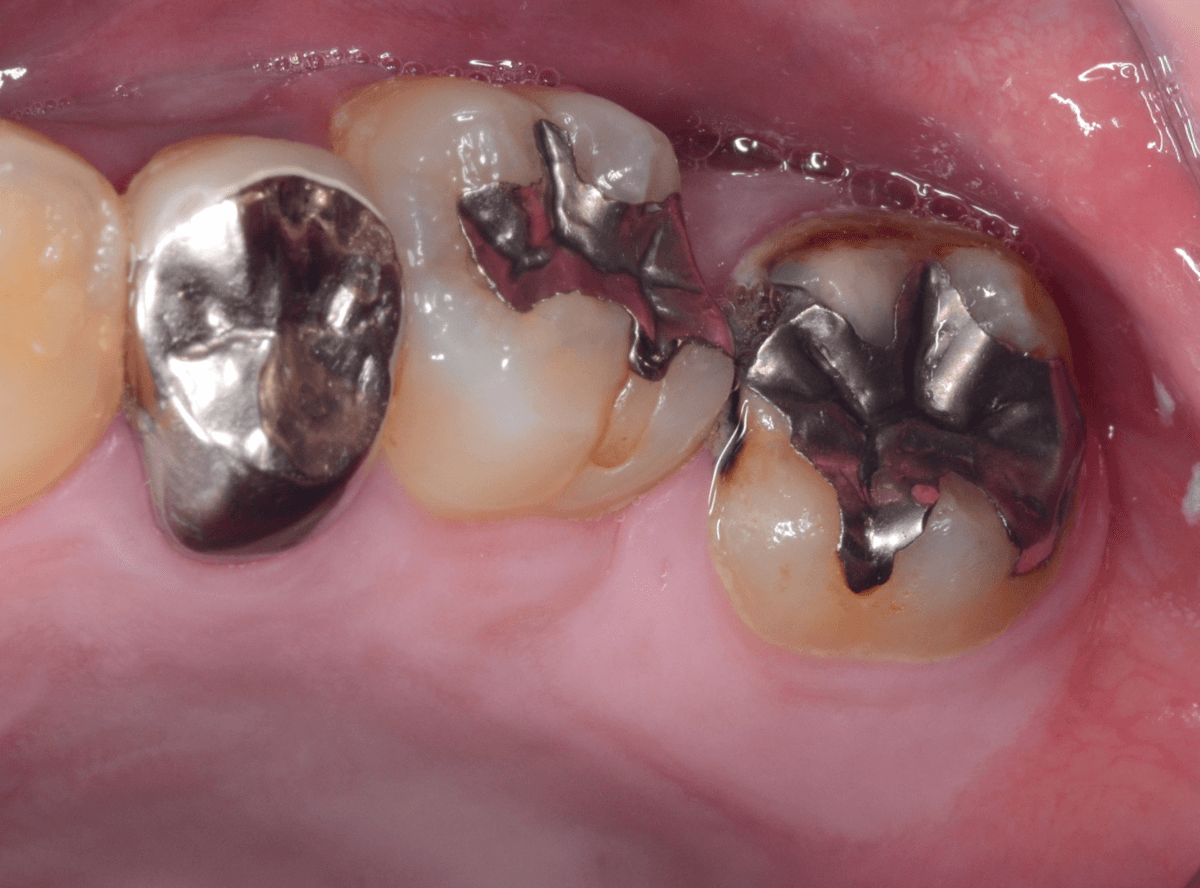

Case.16 金属の周りであちこちから虫歯

検診を希望された患者さんのケースです。

お口の中を拝見すると、上の奥歯の歯のすき間(隣接面)や、変色したレジンの中が怪しい感じです。

レントゲン写真で確認します。

青い線が神経で、赤い線が虫歯と思われる部分です。

奥から3歯が虫歯と思われますが、特に中央の歯の虫歯が深そうです。

まず、中央の歯の金属を除去します。

〇部分は前の治療時にしいたセメントです。この下に虫歯が広がっていると思われます。